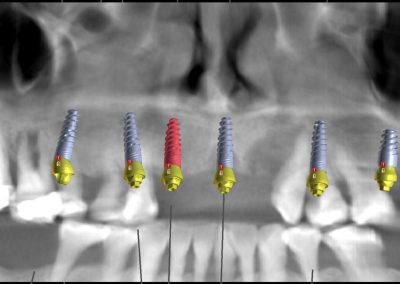

La intervención se realizó bajo anestesia general y contempló la extracción de la totalidad de los dientes del maxilar superior debido a una enfermedad periodontal avanzada, junto con la instalación simultánea de seis implantes dentales mediante cirugía guiada por planificación digital. En este caso, no se efectuó carga inmediata: el plan considera una carga temprana dentro del proceso de rehabilitación.

Uno de los aspectos más destacados fue que, en el mismo acto quirúrgico, se realizó la toma de la impresión para enviar a confeccionar una estructura provisoria completa (con la totalidad de los dientes maxilares), diseñada y elaborada mediante un proceso digital, lo que permite acortar tiempos y aumentar la precisión en etapas clave del tratamiento.